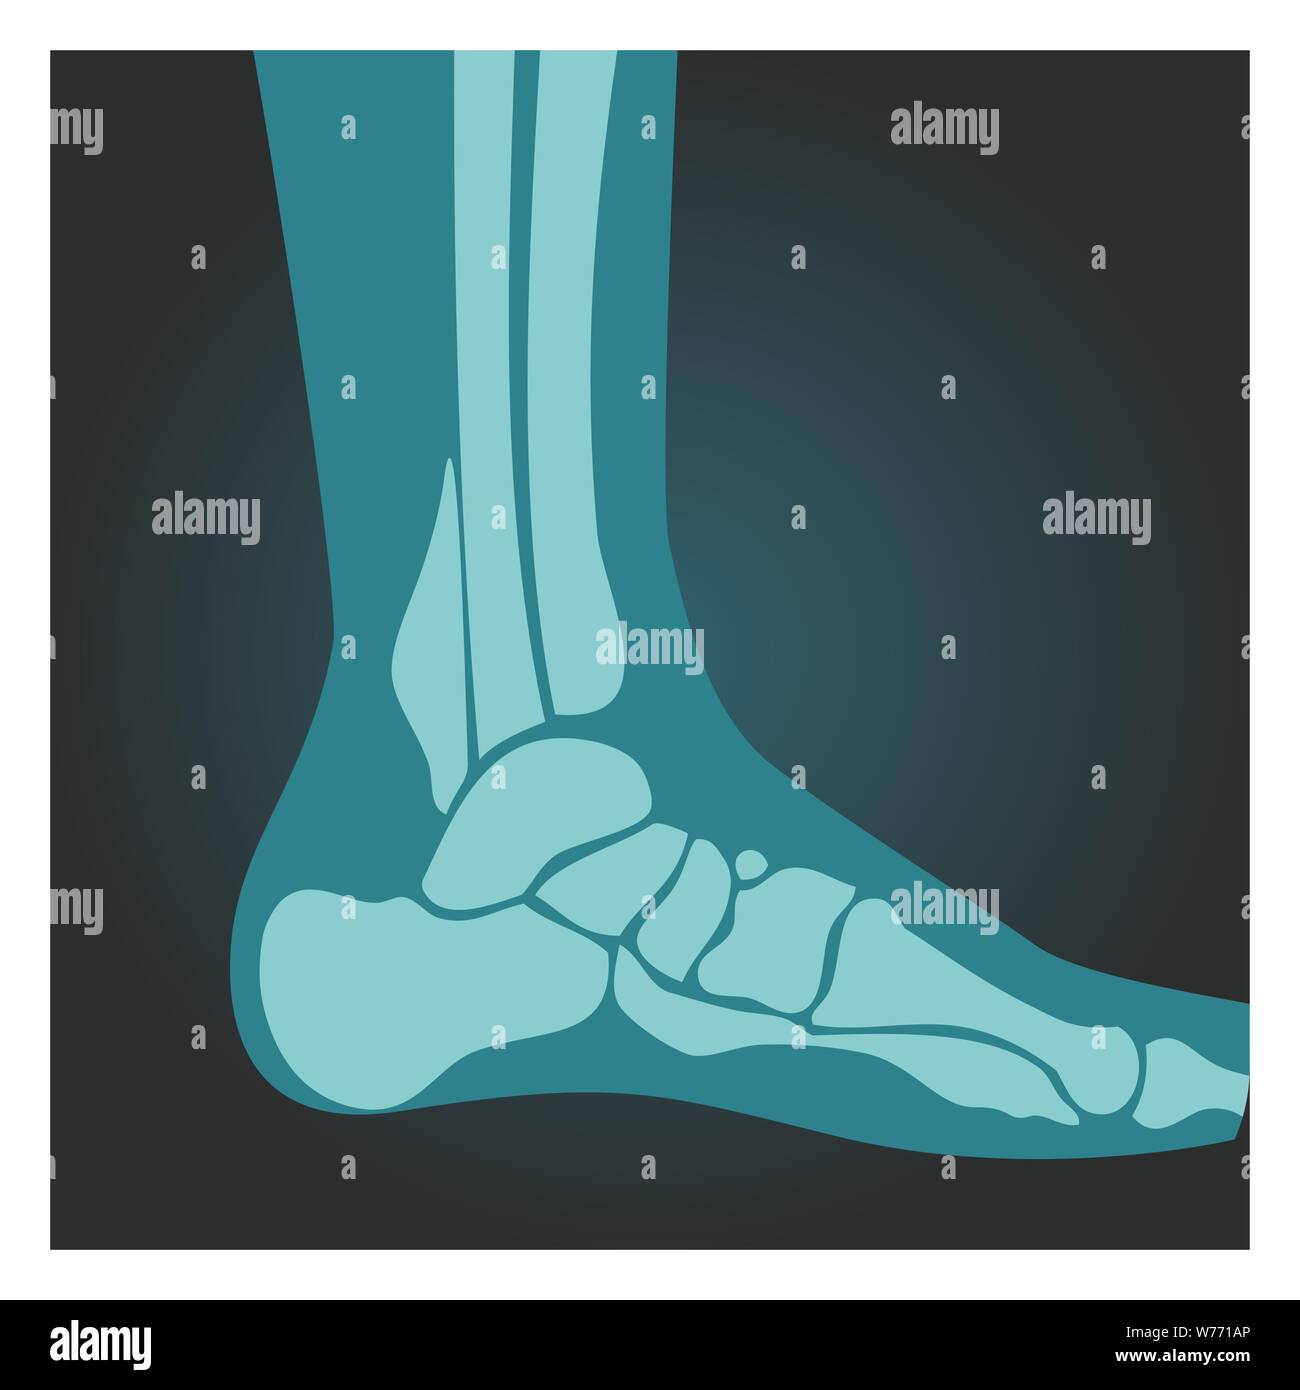

RFW771AP–Émission de rayons X de pied vue latérale, corps humain, les os, radiographie, vector illustration.